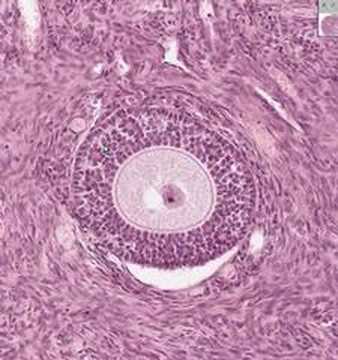

Mammal Ovary Slide, Thin sec, H&E

Product review & video